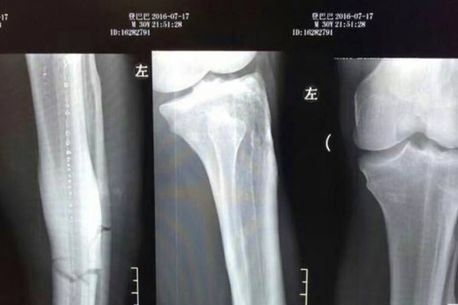

În minutul 64 al meciului, Demba Ba a încercat o demarcare pentru a fi pus în poziție de finalizare. Faza s-a sfârșit nefericit pentru atacant, care a fost călcat de fundașul advers, Sun Xiang, iar tibia a fost cea care a avut de suferit. Senegalezul a fost anesteziat complet la spital, din cauza durerii, iar radiografia făcută la picior arată gravitatea situației.